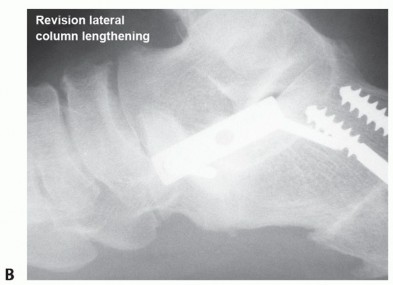

Complications

Nonunion (FIG 8) or malunion Graft fracture or displacement Painful retained deep hardware

FIG 8 • A. Radiograph of late graft nonunion and hardware failure. B. Radiograph showing healed revision with plate fixation.*